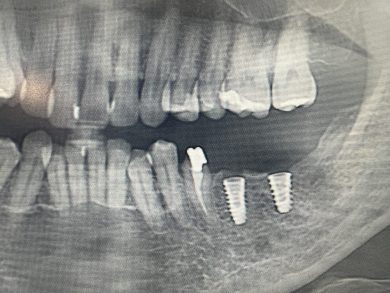

執刀したのは、勤務医のM先生。彼にとって、昨日は人生で初めてのインプラント埋入手術でした。ガイドサージェリー全盛ですが、かれはフリーハンドで完璧にオペしました。

左下に2本。最遠心にはテンポラリーインプラントを入れて、患者さんは手術当日から咬めるようになりました。